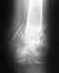

Ищу хирурга, кто оперирует старый(4 недели) вколоченный перелом со смещением головки плечевой кости. Желательно в Москве.